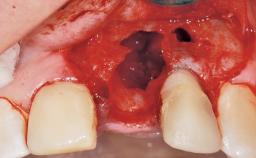

A 29-year-old female patient presented for treatment to replace the upper left central incisor tooth with an implant- supported restoration. The tooth had been intermittently symptomatic for the previous 12 months. The tooth had originally suffered trauma about 15 years previously. Several endodontic treatments had been performed, including an apicectomy procedure to retain the tooth. The patient was healthy and a non-smoker. She had reasonable expectations in regard to esthetic outcomes and the risk of marginal tissue recession following treatment. At medium smile, the gingival margins of the upper teeth were visible, with a display of 3 to 4 mm of the gingival margins. Gingival recession of tooth 21 and a discrepancy in the gingival levels between teeth 11 and 21 was observable during normal speech and smile.

Placement Protocol Immediate implant placement

Socket Integrity Damage to one or more bone walls

Bone Volume Damage to one or more socket walls